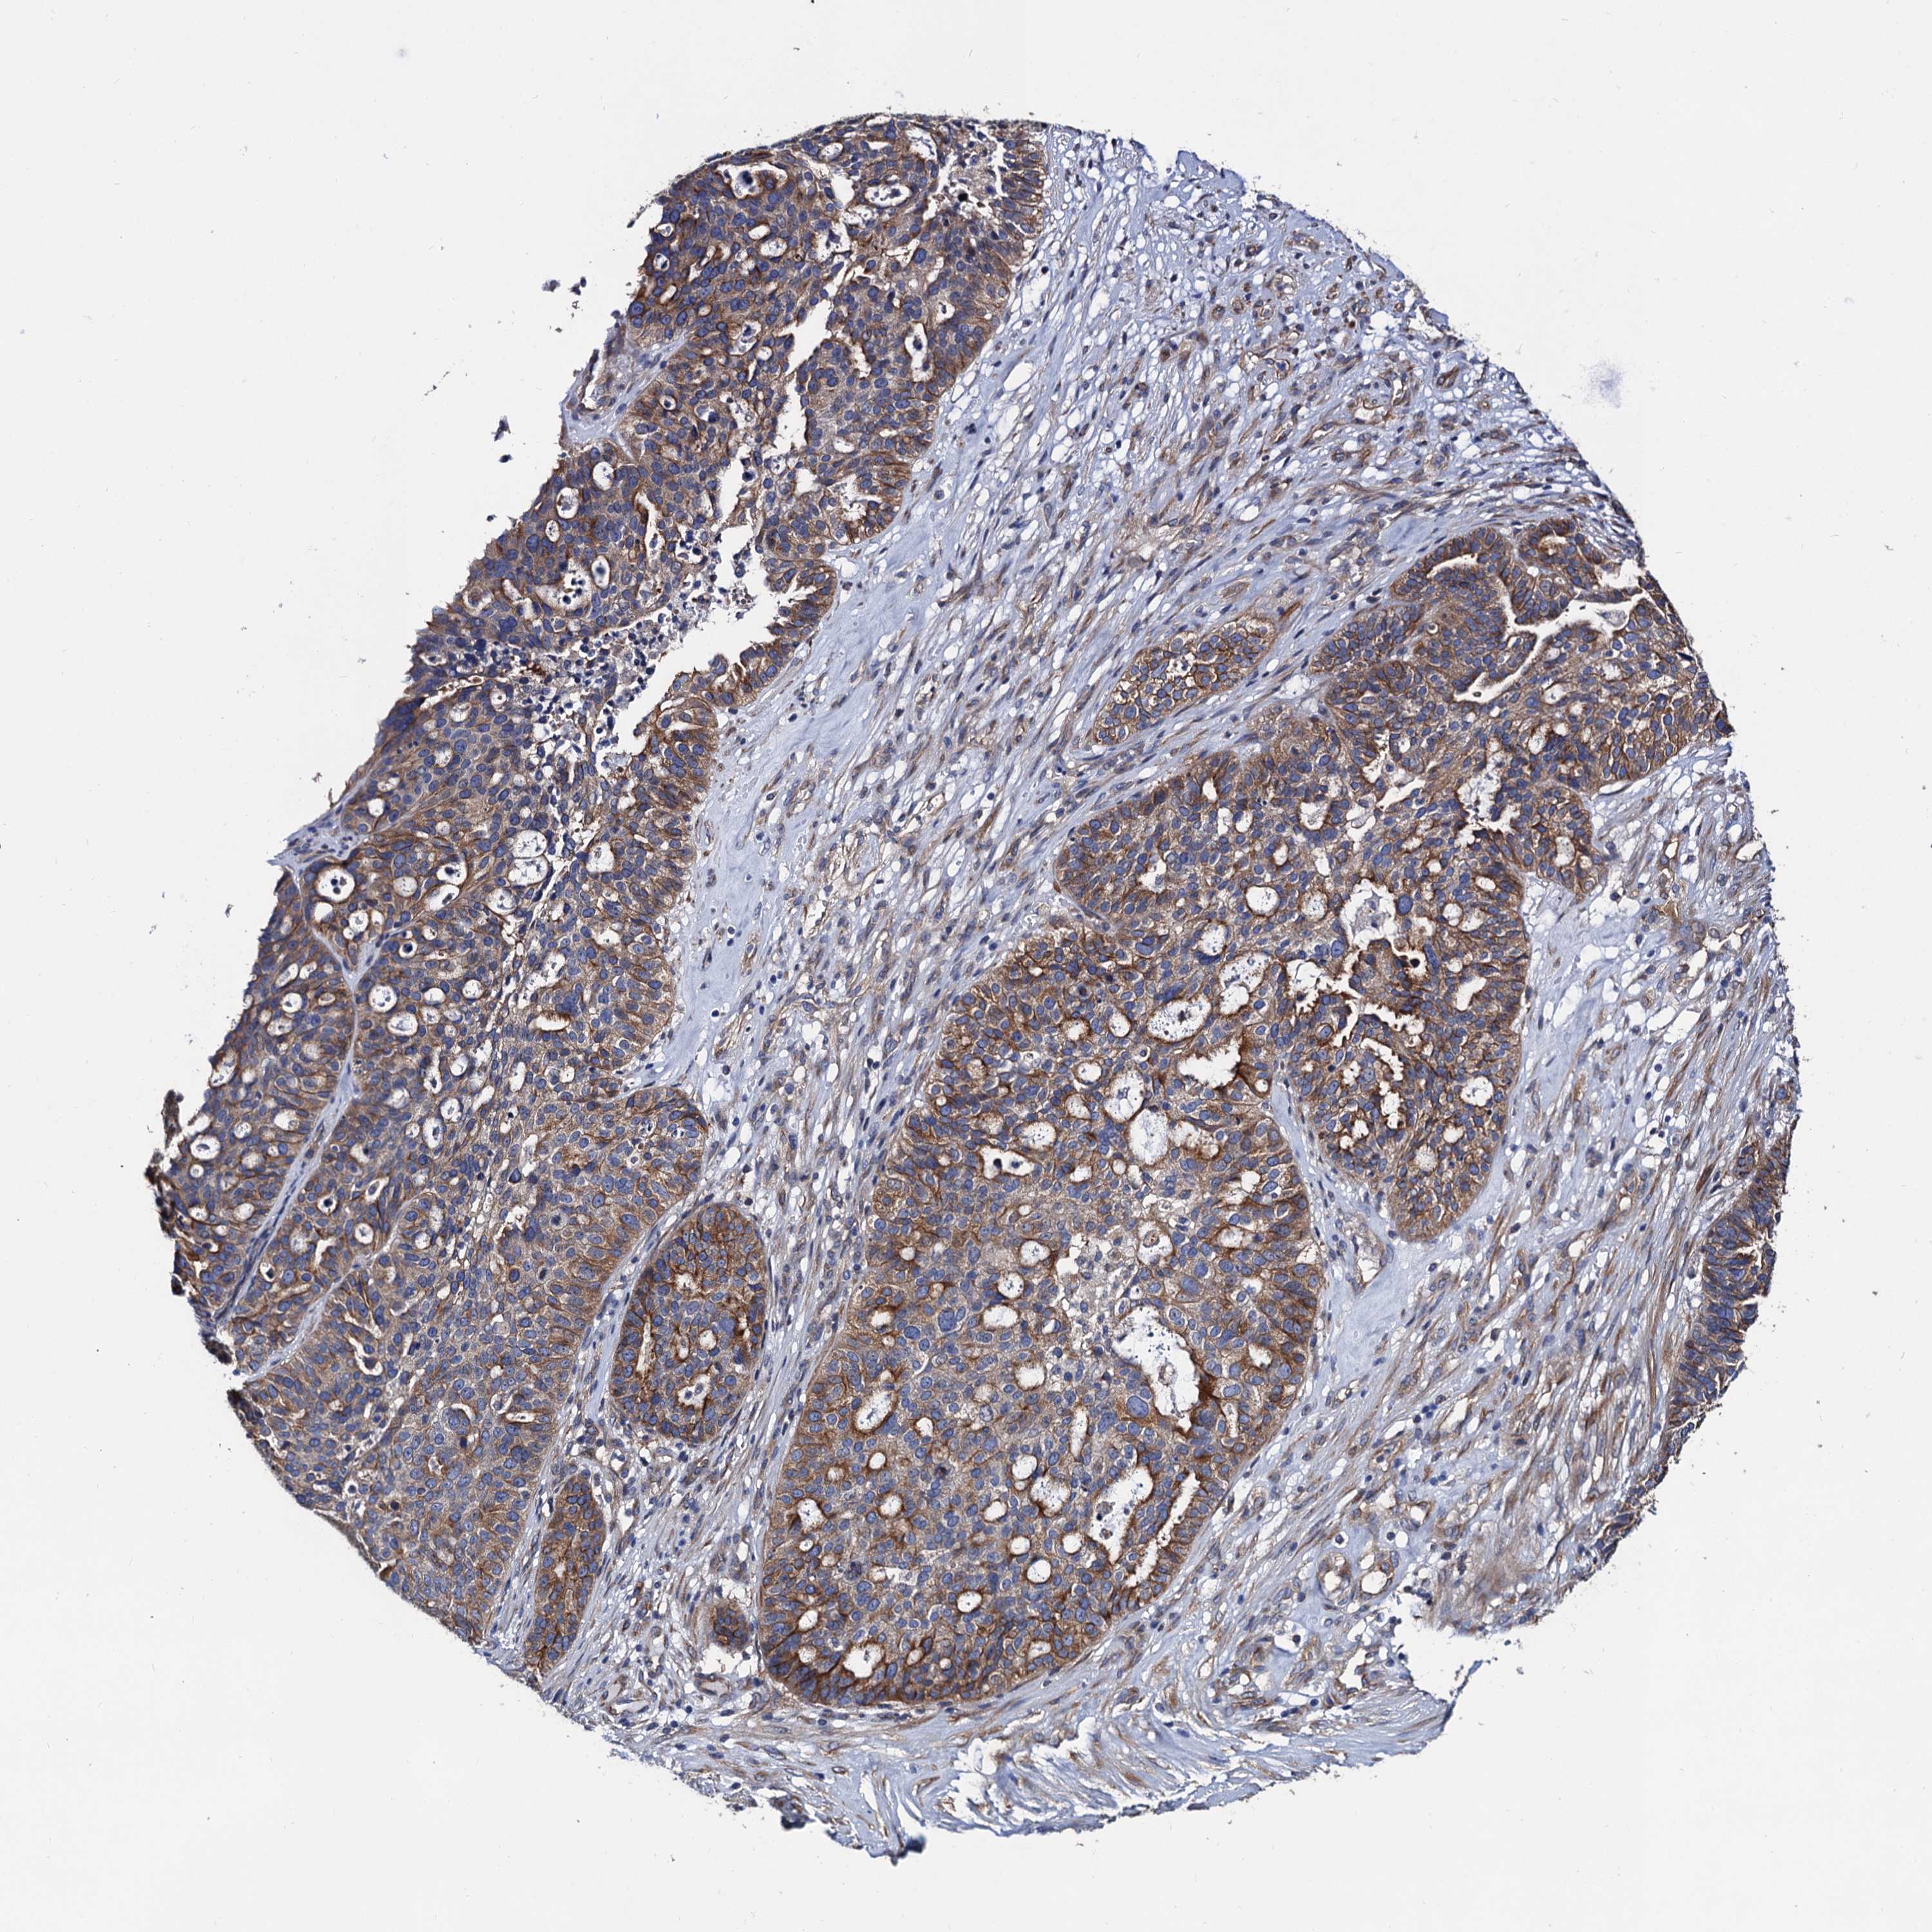

OVARIAN CANCER - Protein expressioni

A mouse-over function shows sample information and annotation data. Click on an image to view it in a full screen mode. Samples can be filtered based on level of antibody staining by selecting one or several of the following categories: high, medium, low and not detected. The assay and annotation is described here.

Note that samples used for immunohistochemistry by the Human Protein Atlas do not correspond to samples in the TCGA dataset.

Antibody stainingi

Antibody staining in the annotated cell types in the current human tissue is reported as not detected, low, medium, or high, based on conventional immunohistochemistry profiling in selected tissues. This score is based on the combination of the staining intensity and fraction of stained cells.

Each image is clickable and will lead to virtual microscopy that enables deeper exploration of all samples and also displays staining intensity scores, fraction scores and subcellular localization as well as patient and tissue information for each sample.

Antibody HPA040234

Staining

High

Medium

Low

Not detected

Intensity

Strong

Moderate

Weak

Negative

Quantity

>75%

75%-25%

<25%

None

Location

Nuclear

Cytoplasmic/membranous

Cytoplasmic/membranous,nuclear

Cystadenocarcinoma, serous, NOS

Carcinoma, endometroid

Cystadenocarcinoma, mucinous, NOS

Carcinoma, NOS